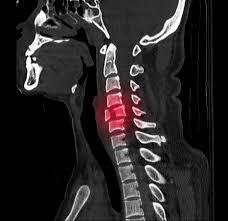

Dieser Bereich stellt den oberen Teil der Wirbelsäule dar der aus den Wirbelkörpern Bandscheiben Muskeln Bändern und den Nervenbahnen besteht. Der erste Halswirbel wird als Atlas bezeichnet der zweite als Axis. Denn der Eingriff birgt Risiken gerade für ältere Betroffene die Operationen nicht mehr so gut verkraften.

Diese Wirbelbrüche sind zwar nicht instabil und die Gefahr von Schäden am Rückenmark ist sehr gering dennoch können sie starke Schmerzen und eine Fehlstellung der Wirbelsäule verursachen. Er kann an einem der sieben Halswirbel entstehen. Bei jüngeren Betroffenen sind in der Regel Verkehrs- und Sportunfälle die Ursachen für einen Wirbelbruch bei älteren Menschen geht ein Wirbelbruch vor allem auf eine schwache Knochenstruktur durch Osteoporose zurück.

Es kann also schon 2 - 3 Monate dauern bis die Wirbelsäule wieder voll belastungsfähig ist. Weil der Wirbelsäulenkanal der Halswirbelsäule sehr eng ist wird bei der Verletzung in 70 Prozent der Fälle zusätzlich auch das Rückenmark geschädigt. Ob ein operativer Eingriff notwendig ist und welche Art von Operation durchgeführt wird hängt einerseits von der Art des Wirbelbruchs andererseits aber auch von den sonstigen Umständen ab.

Bei Halswirbelbrüchen ist eine Zervikalstütze Halskrause notwendig. Unter einem Genickbruch versteht man allgemein einen Bruch der Halswirbelsäule.

Er kann an einem der sieben Halswirbel entstehen. Der erste Halswirbel wird als Atlas bezeichnet der zweite als Axis. Dieser Bereich stellt den oberen Teil der Wirbelsäule dar der aus den Wirbelkörpern Bandscheiben Muskeln Bändern und den Nervenbahnen besteht. Denn der Eingriff birgt Risiken gerade für ältere Betroffene die Operationen nicht mehr so gut verkraften. Er kann an einem der sieben Halswirbel entstehen. Die Schmerzen können einen älteren Menschen ans Bett fesseln und seiner Mobilität berauben und hier lauert die eigentliche Gefahr. Nur 15 bis 20 Prozent aller Wirbelsäulenverletzungen betreffen die Halswirbelsäule. Unter einem Genickbruch versteht man allgemein einen Bruch der Halswirbelsäule. Diese Wirbelbrüche sind zwar nicht instabil und die Gefahr von Schäden am Rückenmark ist sehr gering dennoch können sie starke Schmerzen und eine Fehlstellung der Wirbelsäule verursachen.

Beschreibung Ein Genickbruch bezeichnet einen Wirbelbruch der Halswirbelsäule. Bei einem jungen Sportler ist man eher geneigt eine Operation durchzuführen als bei einem alten bettlägrigen Patienten den man so ohne großen Nutzen für die Dauer von weiteren 2 Monaten in ein. Bei einem Wirbelbruch durch Osteoporose raten viele Ärzte zu einer Operation. Nur 15 bis 20 Prozent aller Wirbelsäulenverletzungen betreffen die Halswirbelsäule. Bei instabilen Brüchen besteht dagegen die Gefahr dass Teile des Bruches die Nervenwurzel im Spinalkanal einengen und dadurch neurologische Ausfälle wie Lähmungen folgen. Weil der Wirbelsäulenkanal der Halswirbelsäule sehr eng ist wird bei der Verletzung in 70 Prozent der Fälle zusätzlich auch das Rückenmark geschädigt. Der erste Halswirbel wird als Atlas bezeichnet der zweite als Axis.